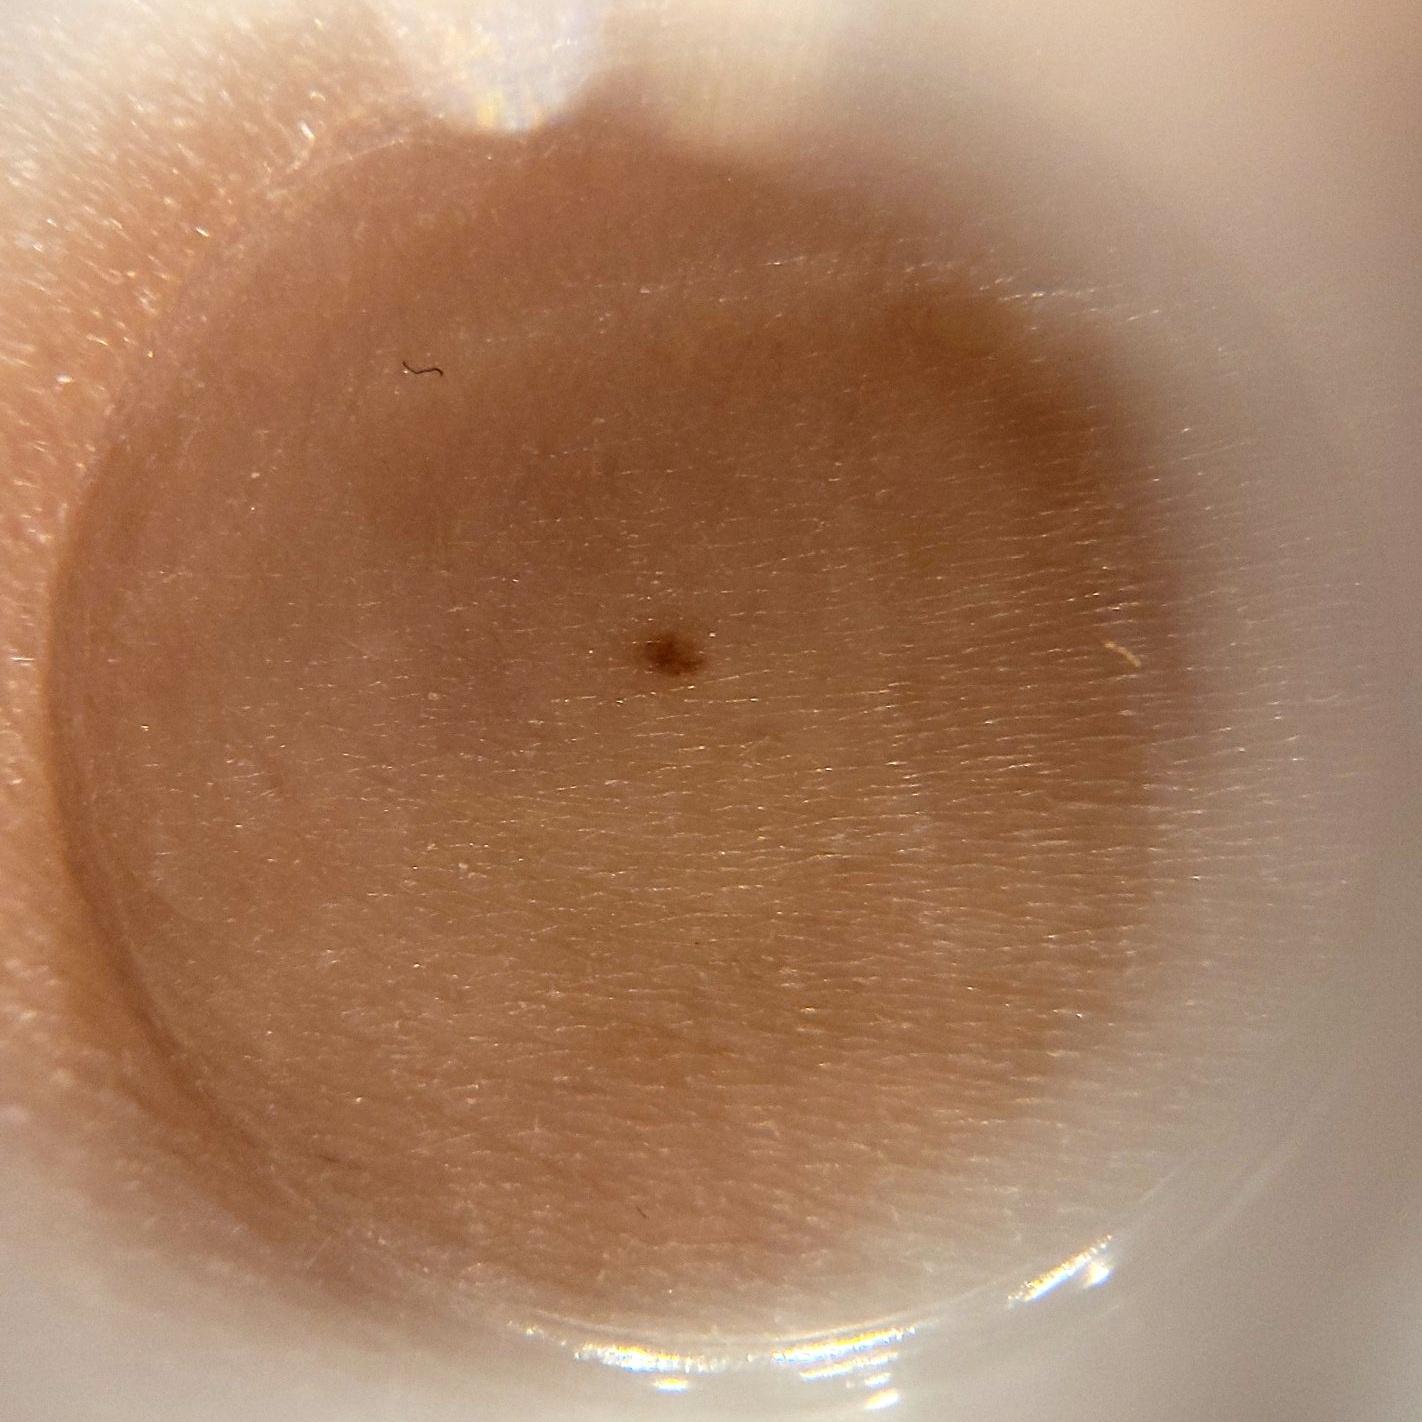

ISIC_1803958

1422 x 1422

Clinical

Field Value

acquisition_day 112

age_approx 45

anatom_site_1 Upper extremity

anatom_site_general upper extremity

diagnosis_1 Benign

diagnosis_confirm_type single image expert consensus

image_type dermoscopic